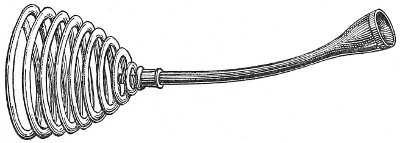

The uterine sound is an instrument by which the length of the uterine cavity may be determined (Fig. 15). The sound, which is a large surgical probe, somewhat curved to adapt itself to the normal shape of the uterine axis, is made of pliable metal, so that the curvature may be changed readily to suit any case. The sound is graduated, and at a position of 2½ inches from the tip is a small elevation marking the length of the normal uterine cavity.

Fig. 15.—Uterine sound.

The uterine sound was at one time used a great deal to determine the length and direction of the uterus, and 35 perhaps to assist in determining the character of the uterine contents or of the endometrium. With our present methods of examination, however, the sound is of but little if any use. The size and direction of the uterus can in nearly all cases be determined by bimanual examination. The use of the uterine sound is by no means free from danger. Many cases of septic endometritis and salpingitis have been caused by it, and the physician has often unintentionally committed an abortion by passing the sound in a pregnant woman. The uterine sound should never be used in a routine way. It should never be used unless one expects to determine with it something that cannot be determined by simpler methods of examination.

The most thorough aseptic precautions should be observed when the sound is introduced. The vulva, vagina, and cervix should be cleaned and the sound should be sterilized. The sound should never be introduced if there is any suspicion of pregnancy.